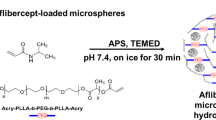

A Dex dimer was synthesized through a one-step synthesis, using a triethylene gycol (TEG) linker and two Dex molecules (Dex-TEG-Dex) (Fig. 1a, Supplementary Figure 1). Structures were confirmed by nuclear magnetic resonance spectroscopy (NMR) (Supplementary Fig. 1) and mass spectrometry (m/z: [M + H]+ Calculated for C52H69F2O16 987.4554; Found 987.4549). Due to its simple design and the ability to synthesize the dimers as monodisperse entities, Dex-TEG-Dex has well-defined degradation products (free Dex, Dex-TEG, TEG, CO2). The melting point (Tm) of Dex-TEG-Dex was 167 °C, in comparison to a Tm of 262 °C for Dex27. While the synthesis of drug conjugates has been reported in the literature, this synthetic approach is typically pursued for the purpose of changing drug solubility, biodistribution, or increasing half-life when administered as solubilized compounds28. In contrast, the utility of the disclosed dimers is their ability to be fabricated into stand-alone implants. When Dex-TEG-Dex is processed using established techniques, it yields amorphous engineered shapes and forms. Processability of Dex-TEG-Dex was demonstrated using standard heat29,30 and solvent30,31,32 polymer processing methods. Importantly, no additives, polymers, excipients, or other agents, routinely required to physically stabilize drugs into a formed implant, were needed in the manufacturing process30,31,32,33. Heat-based processing was used to form fibers (fiber pulling), device coatings (powder coating), and rods (melt extrusion) (Fig. 1b). Common solvent-based approaches were used to successfully generate polymer and excipient free drug dimer materials, including fibrous meshes (electrospinning), microparticles (electrospraying, emulsion), nanoparticles (emulsion, Supplementary Fig. 2), and medical device coatings (spray coating, dip coating, solvent casting) (Fig. 1b).

a Schematic demonstrating the general form of the dimers, and the chemical structure of a representative dimer molecule made with the corticosteroid dexamethasone using a triethylene glycol (TEG) linker. (b Transmission electron microscopy (nanoparticles), light micrographs (coatings), and scanning electron microscopy (SEM) (all others) images demonstrating steroid dimers processed into different physical forms through thermal processing (fibers, coatings, extruded rods) and solvent processing (nanoparticles, microparticles, fibers, coatings, fibrous meshes).